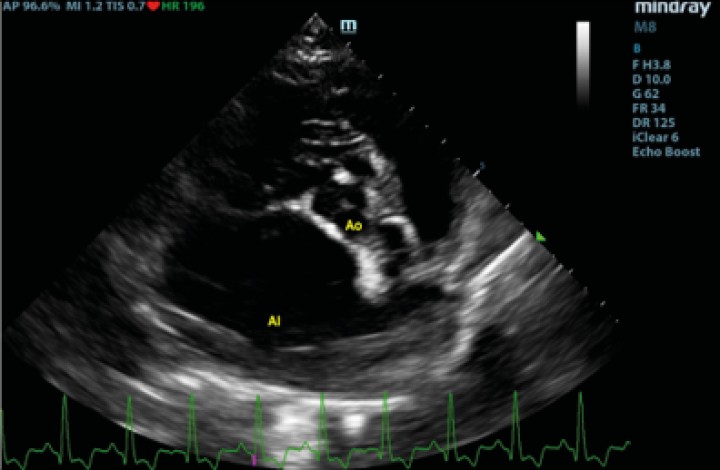

Ecocardiográficamente se observó una dilatación severa del atrio izquierdo (AI) (ratio aorta/atrio izquierdo[ Hansson K, Häggström J, Kvart C, Lord P. Left atrial to aortic root indices using two-dimensional and M-mode echocardiography in cavalier King Charles spaniels with and without left atrial enlargement. Vet Radiol Ultrasound 2002; 43(6): 568-575. [PubMed] ] de 3,88; diámetro normalizado del atrio izquierdo[ Marchesotti F, Vezzosi T, Tognetti R, et al. Left atrial anteroposterior diameter in dogs: reference interval, allometric scaling, and agreement with the left atrial-to-aortic root ratio. J Vet Med Sci 2019; 81(11): 1655-1662. [PubMed] ] de 26,91) y dilatación del ventrículo izquierdo (diámetro interno del ventrículo izquierdo normalizado en diástole[ Cornell CC, Kittleson MD, Della Torre P, et al. Allometric scaling of M-mode cardiac measurements in normal adult dogs. J Vet Intern Med 2004; 18(3): 311-321. [PubMed] ] de 2,28) secundarios a un engrosamiento, fallo de coaptación y prolapso de las valvas de la válvula mitral, determinando una regurgitación mitrálica posterior grave. Se realizó radiología torácica para valorar la presencia de edema pulmonar, observando un patrón intersticial-alveolar severo en el área perihiliar y en los lóbulos caudales pulmonares, compatible con la presencia de edema pulmonar de origen cardiogénico. Tras la realización de la radiografía torácica, se diagnosticó ECDVM en estadio C[ Keene BW, Atkins CE, Bonagura JD, et al. ACVIM consensus guidelines for the diagnosis and treatment of myxomatous mitral valve disease in dogs. J Vet Intern Med 2019; 33(3): 1127-1140. [PubMed] ] agudo, con una puntuación ecocardiográfica de la insuficiencia mitral (MINE)[ Vezzosi T, Grosso G, Tognetti R, et al. The Mitral Insufficiency Echocardiographic score: A severity classification of myxomatous mitral valve disease in dogs. J Vet Intern Med 2021; 35(3): 1238-1244. [PubMed] ] de 12. No se observó derrame pericárdico durante la realización del examen (Figs. 1 y 2).

<p>Corte paraesternal derecho transversal a la altura del atrio izquierdo y aorta, previo a la rotura del atrio izquierdo. Ao: aorta; AI: atrio izquierdo.</p>

Figura 2

Corte paraesternal derecho transversal a la altura del atrio izquierdo y aorta, previo a la rotura del atrio izquierdo. Ao: aorta; AI: atrio izquierdo.